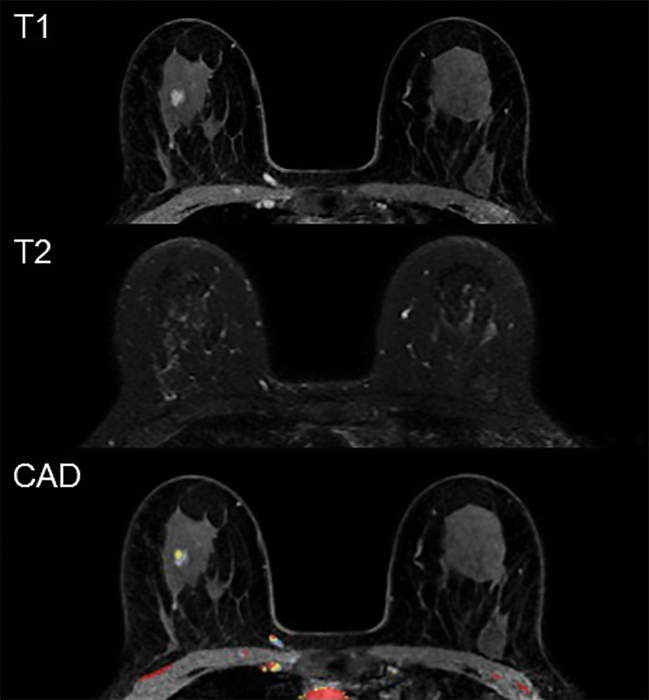

OAK BROOK, Ill. – Prediction models based on clinical characteristics and imaging findings may help reduce the false-positive rate in women with dense breasts who undergo supplemental breast cancer screening with MRI, according to a new study in the journal Radiology .

For these reasons, breast MRI is considered a potentially useful supplement to mammography screening in women with dense breast tissue. It is the most sensitive imaging technique for diagnosing breast cancer and can differentiate well between lesions and abnormalities of the breast. Research has confirmed its substantial added value as a screening tool for women at high risk of breast cancer.

However, the high sensitivity that makes MRI an excellent screening tool also means it often detects benign lesions that otherwise would have gone unnoticed. Women who get recalled for additional work-up based on these findings potentially face repeat MRI scans, targeted ultrasound and biopsy. The need for additional investigations may cause anxiety in the patient, increase health care costs or lead to biopsy-related complications.

In the new study, Dr. den Dekker and colleagues developed prediction models to distinguish true-positive MRI screening from false-positives. To create the models, they combined MRI findings with clinical characteristics like body mass index, family history of breast cancer and use of hormone replacement therapy.